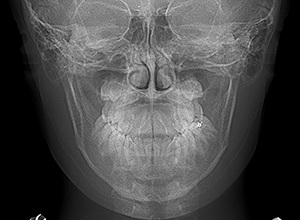

| X-Ray所見 | |

| セファロ所見 | Sellaに対して下顎頭は後方位だが下顎骨は大きくしっかりとした形態をしており前後的にはⅠ級、垂直的にはロウアングルの骨格形態をしていた。 上顎前歯は唇側傾斜を呈していた。 |

| パノラマ所見 | 上顎左右側犬歯は近心傾斜し側切歯歯根に重なるように認められた。 |